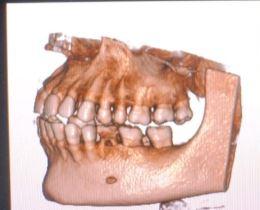

Cbct in delhi ncr, new delhi Cone Beam Computed To...

Dental scan near me c-8/193 sector 8 rohini delhi...

View DetailsCBCT IN DELHI C-8/193 SECTOR 8 ROHINI DELHI-110085...

CBCT test in rohini#delhi NCR CBCT stands for con...

CBCT IN DELHI C-8/193 SECTOR 8 ROHINI DELHI-110085...

Cbct scan near me Dr. Mittal's Diagnostic centre s...

CBCT in delhi CBCT in rohini CBCT stands for cone...